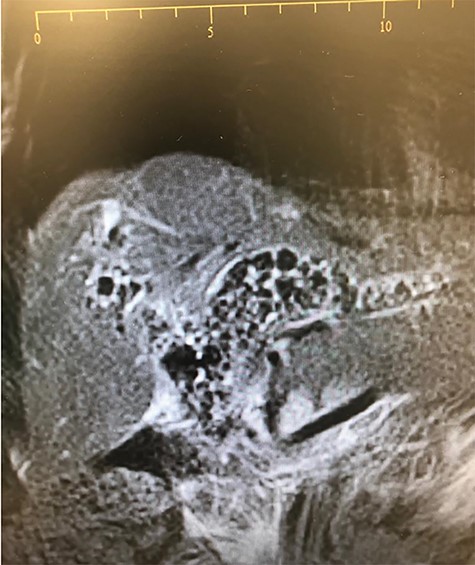

We present a 79-years-old female patient who presented on the 31 January 2019 with worsening recurrent right upper quadrant pain, dark urine, chills and tiredness for 12 months. She was a known diabetic and hypertensive controlled on medications. Her past surgical history was notable for having had an open cholecystectomy for symptomatic cholelithiasis in 2016. The same year post cholecystectomy, she was found to have retained common bile duct (CBD) stones. She had endoscopic retrograde cholangiopancreatography (ERCP), during which a complete clearance of the stone was not achieved and she was stented with a completely covered metal stent. There was no follow-up until she got symptomatic in 2019 and she presented with cholangitis. Her blood workup showed an obstructive picture. The abdominal ultrasound was not diagnostic. She was started on analgesia and antibiotics. A differential diagnosis of a blocked stent was made. She had an ERCP on the 04 February 2019. An old stent was found, which could not come out. An extraction balloon was used to clean the old stent of debris and small stones and a 10 Fr × 9 cm plastic stent was deployed. On table, cholangiogram showed dilated ducts with multiple stones in the CBD extending into the left and right hepatic ducts and the first order ducts bilaterally (Fig. 1). MRCP confirmed the cholangiogram findings (Fig. 2). On 18 February 2019, she had open bile duct exploration and Roux-en-Y hepaticojejunostomy reconstruction (wide anastomosis). The stents and multiple stones were removed (Fig. 3). She had an uneventful post-operative course. At her first follow-up, 6 weeks later, she had normal liver function tests and felt much better.